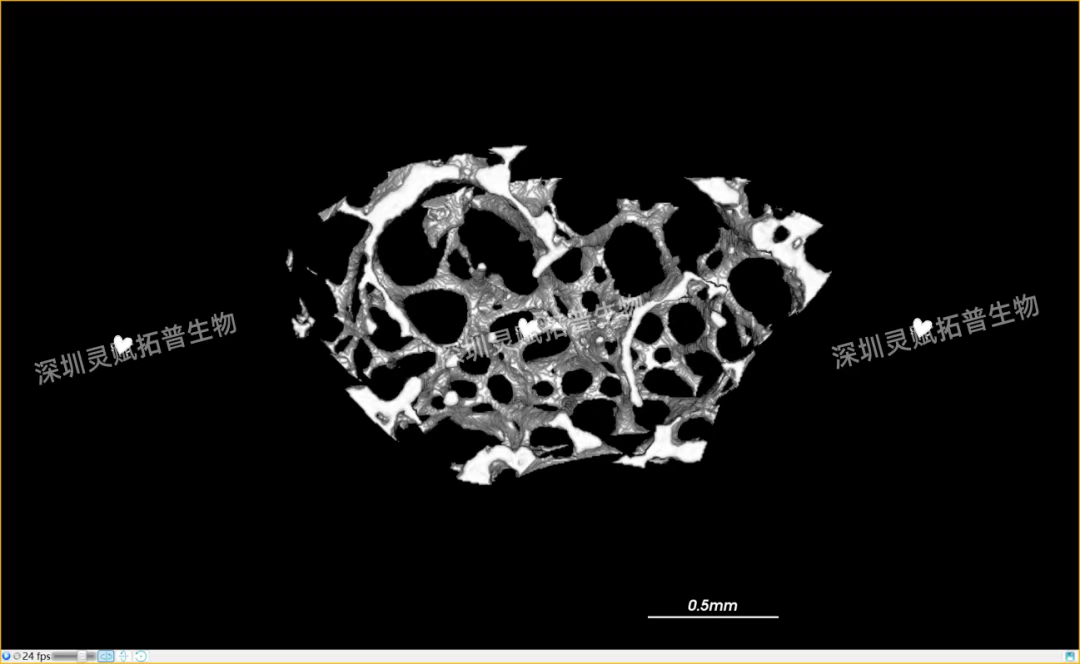

本次实验对 E2 系列(E2-1、E2-2、E2-3)共3个小鼠股骨样本进行标准化扫描,取得了 0.5mm、2mm 等不同尺度的清晰成像,不仅直观呈现了股骨的宏观形态,更精准捕捉到骨小梁排列、皮质骨厚度等微观细节,为后续骨质疏松、骨修复等相关研究给予了可靠的量化数据支撑。

下附E2系列的典型案例:小鼠股骨扫描成像图